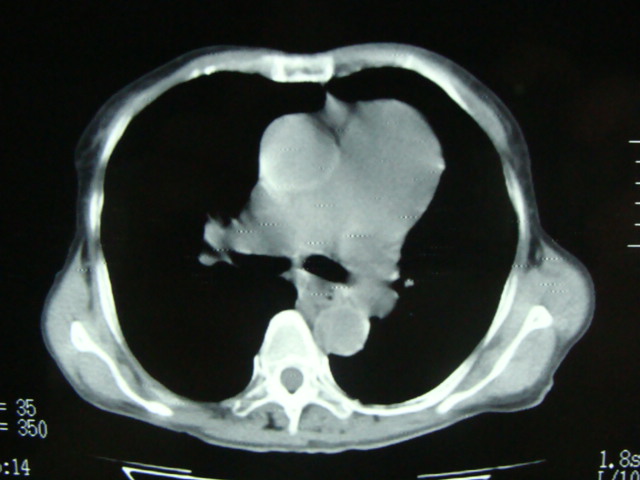

以下是引用老爱克斯新网客在2008-6-2 6:38:00的发言:[br]ct表现是肺动脉根部明显扩张,右心室增大,左房左室及右房都不大,因此可以除外风心。高血压心脏病。冠心病。定位片基本可以除外肺心病,(心肌病。心包积液更不可能)因此除外了后天性获得性心脏病。其表现也可以除外室缺。房缺。动脉导管未闭等常见的先心病。如果是原发性肺动脉高压除肺动脉根部扩张外双侧肺动脉尤其是右下肺动脉干应该也有扩张。因此我认为最大的可能是肺动脉瓣狭窄伴有窄后扩张,建议做一下彩超就知道了。期待结果。